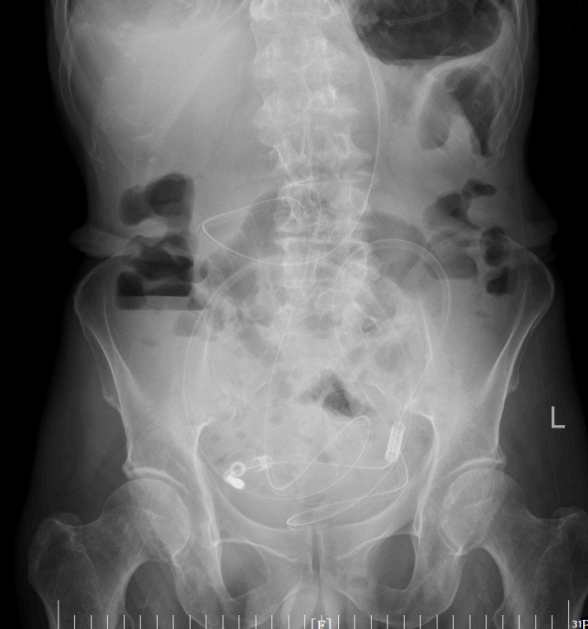

2月11日,手术顺利开展。贺伯伟主任与王志斌副主任医师凭借精湛技术,在DSA引导下精准操作,将导管稳稳置入预定位置。全程严谨把控每一个环节,确保导管位置准确无误。最终,手术顺利完成,老人的“关键通道”被重新打通。

导管开始工作后,积聚的肠内容物被持续引出,腹胀腹痛的症状一天天缓解。老人的肠道功能慢慢恢复,复查腹平片显示梗阻情况明显好转。在护理团队的精心照料下,老人从卧床不起到能下地活动,从禁食禁水到逐渐恢复饮食,一天天好起来。2月24日,王大爷顺利出院,重新回归了正常生活。